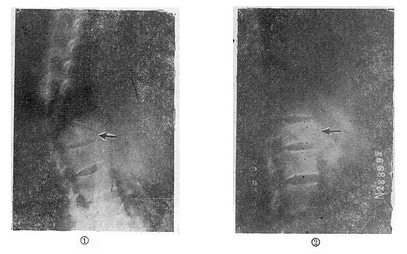

图73-10 攀索叠砖法 (一)单纯楔状压缩骨折的治疗 轻型的压缩骨折,可以采用保守治疗方法。天津医院骨科发掘我国古代医学遗产,创建了“垫枕背伸肌锻炼法”,是一种可行方法(图73-11)。具体做法为病人仰卧硬板床上,腰部用塔形枕垫起,垫枕正对骨折部位,保持脊柱过伸位。先静卧2~3天,待骨折处出血停止,疼痛减轻及腹气胀反应消退后即开始如图示方法,逐渐加强锻炼。病人卧床3个月,天天坚持锻炼,大部分病人可获得良好的结果(图73-12)。此法的缺点是需较长时间的卧床,且对一些比较严重的压缩骨折,有时复位不够满意。我们经验认为,对于椎体前方压缩50%以上者,特别是青年患者,最好用两根Harrington棍进行手术或Dick法复位固定。可以使骨折解剖复位,而且术后两周即可带石膏围腰或支具下地活动。

图73-11 垫枕背伸肌锻炼法

图73-12 垫枕背伸锻炼获良好结果 ①骨折初时;②背伸锻炼3个月后 (二)旋转型脊柱骨折的治疗 用Harrington棍法,不能矫正旋转,最好用Luque棍或Dick法进行矫正与固定。两根“L”型金属棍,放在棘突基底两侧,用每一个椎板下穿过的Luque钢丝固定到骨折部位上、下方各三个椎体椎板上,通过弯好弧度的Luque棍的杠杆作用和拧紧Luque钢丝所产生的矫正力,可以矫正旋畸形,并牢固固定骨折。如不合并神经系统症状,1周后即可下地活动。 (三)爆裂型骨折的治疗 如不合并严重的神经系统症状,损伤又在两周以内者,可以用双Harrington法,撑开矫正,或用Dick手术;可以获得满意的结果(图73-13)。复位后需融合相邻两个椎间隙,因为CT常显示在爆裂型骨折中,相邻的上、下两个椎间盘均有损伤,如不融合,日后取棍后会出现腰痛。使用本法时,如前纵韧带完整,则很容易恢复椎体前方的高度。但爆裂型骨折存在下述三种情况时,需行前路减压术:①合并神经系统症状较重者;②就诊较晚,已两周以上者(常常10天以上就复位比较困难);③脊柱CT扫描显示已有较大的骨折片突出椎管内,使髓腔管变窄超过30%以上者,预示后纵韧带已有明显损伤,使用后路手术方法已无法使骨折片复位。Kostuik复习了日本和多伦多治疗脊柱骨折的结果后证实,前路减压术能使膀胱、肛门及肢体功能得到更好的恢复。